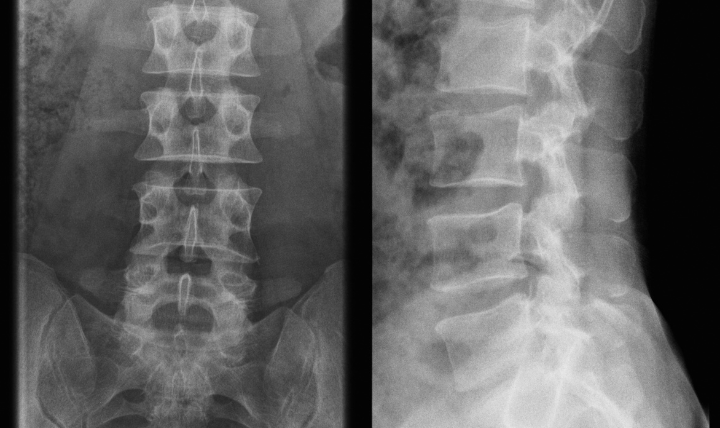

腰椎分離症の正体腰椎分離症とは?反復する「反る・ひねる」動作が引き起こす疲労骨折

人間の腰の骨(腰椎)の後ろ側には、上下の骨を連結する「関節突起間部」という細い架け橋のような部分があります。

野球の投球やバレーボールのスパイク、体操やサッカーなど、スポーツ中に体を「強く反らして、ひねる」動作を繰り返すと、この細い部分に上下の骨がガチガチと衝突します。

成長期の未熟で柔らかい骨にこの物理的な衝突とストレスが蓄積し、微小な亀裂が入って「疲労骨折」を起こした状態が「腰椎分離症」です。